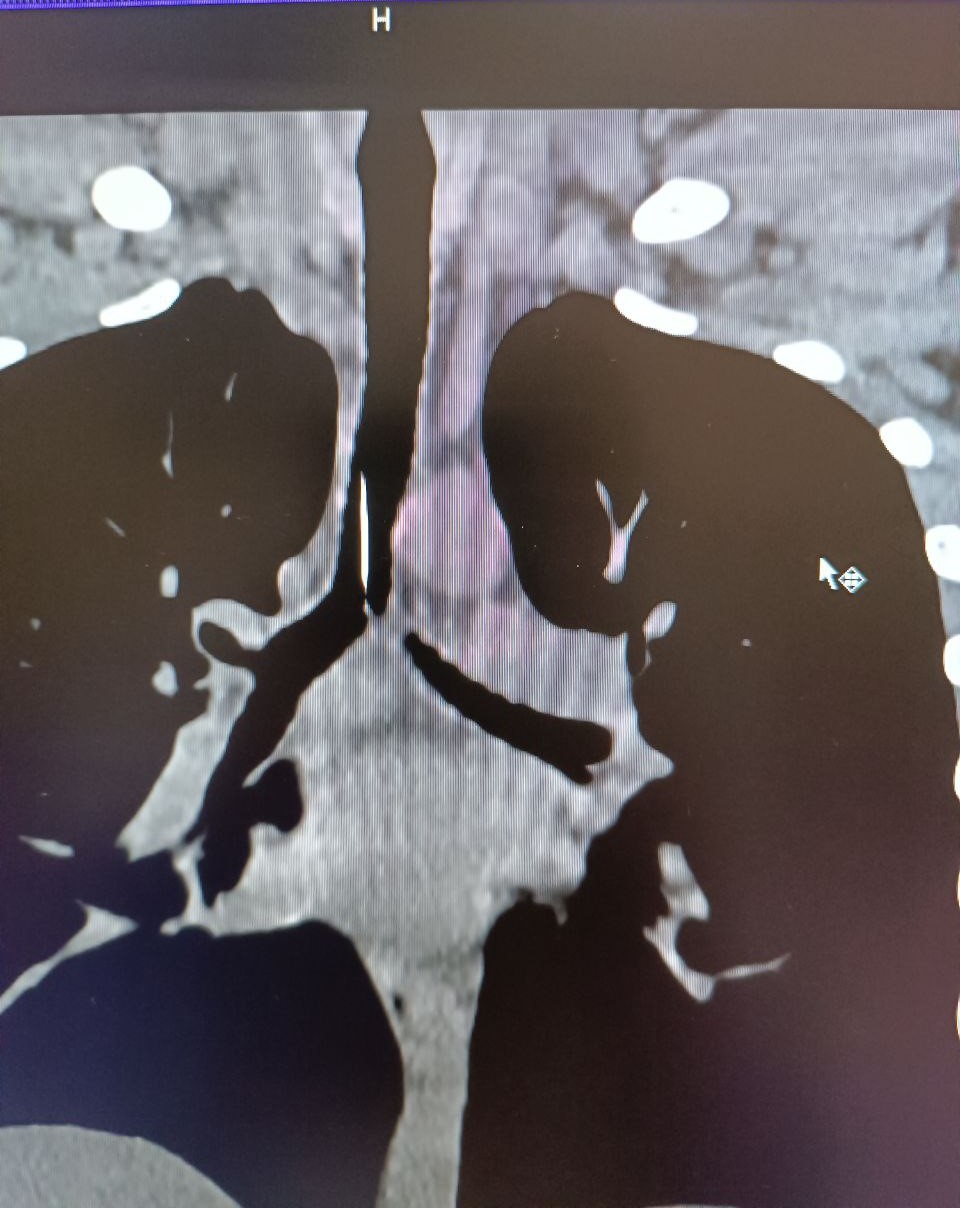

Клинический случай произошел 2 февраля. Подросток был доставлен в приемное отделение городской больницы из одного из поселков района с посторонним телом в трахеи.

Благодаря высокой квалификации дежурного хирурга и анестезиологической бригады, эндоскопическим методом было удалено инородное тело - игла длиной 4 см.

Подростку под наркозом провели бронхоскопию и достали шпильку, которая острым концом вонзилась в слизистую и никуда не двигалась.